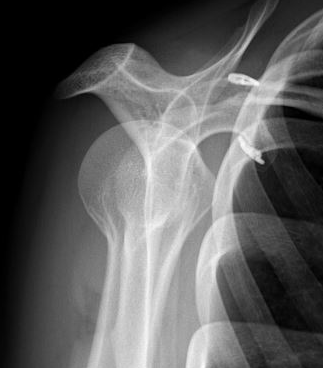

Allman grades I-III 1967 / Rockwood modified 1989 Classification

I AC ligament sprained, but CC ligaments intact (xray normal)

II AC ligament disrupted, CC ligaments sprained but intact (displaced < 100% CC distance)

III AC & CC ligaments ruptured (displaced up to 100% of CC distance)

IV AC and CC ligaments disrupted and clavicle displaced posteriorly into trapezius

V High dislocation (100 - 300% CC distance) - disrupted trapezius & deltoid and end of clavicle subcutaneous

VI Subcoracoid dislocation

X-rays

Zanca view

- specific for AC joint

- 10o cephalad, 50% underpowered

Stress views

- hold weights in each arm

Normal

- 50% of population overriding clavicle

- 2% under riding

- 29% incongruent

- joint width 0.5-7 mm